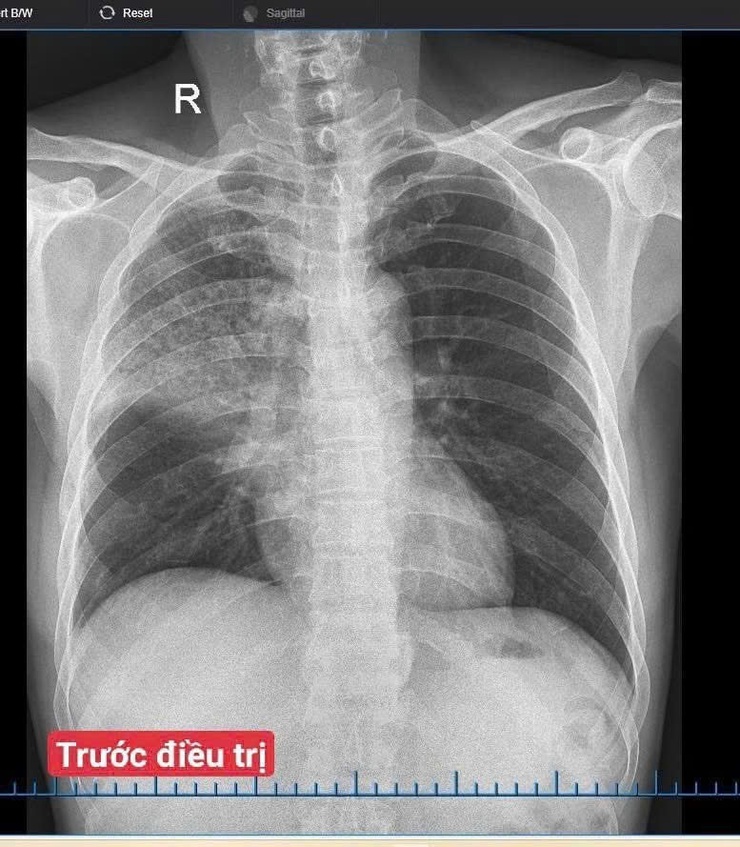

Điều trị thành công ca viêm phổi cộng đồng trên bệnh nhân xơ gan, viêm gan B tại Bệnh viện Đa khoa Vân Đình- Ảnh 1.

Hình ảnh trước và sau điều trị của người bệnh

Bệnh nhân nhập viện trong tình trạng sốt cao, ho nhiều, khạc đờm đục, đau ngực và khó thở. Sau khi thăm khám, làm các xét nghiệm cần thiết, bác sĩ chẩn đoán viêm phổi cộng đồng nặng trên bệnh nhân có bệnh lý gan mạn tính. Người bệnh được điều trị tích cực bằng kháng sinh theo kháng sinh đồ, kết hợp hỗ trợ gan, bù dịch – điện giải và theo dõi sát hô hấp.